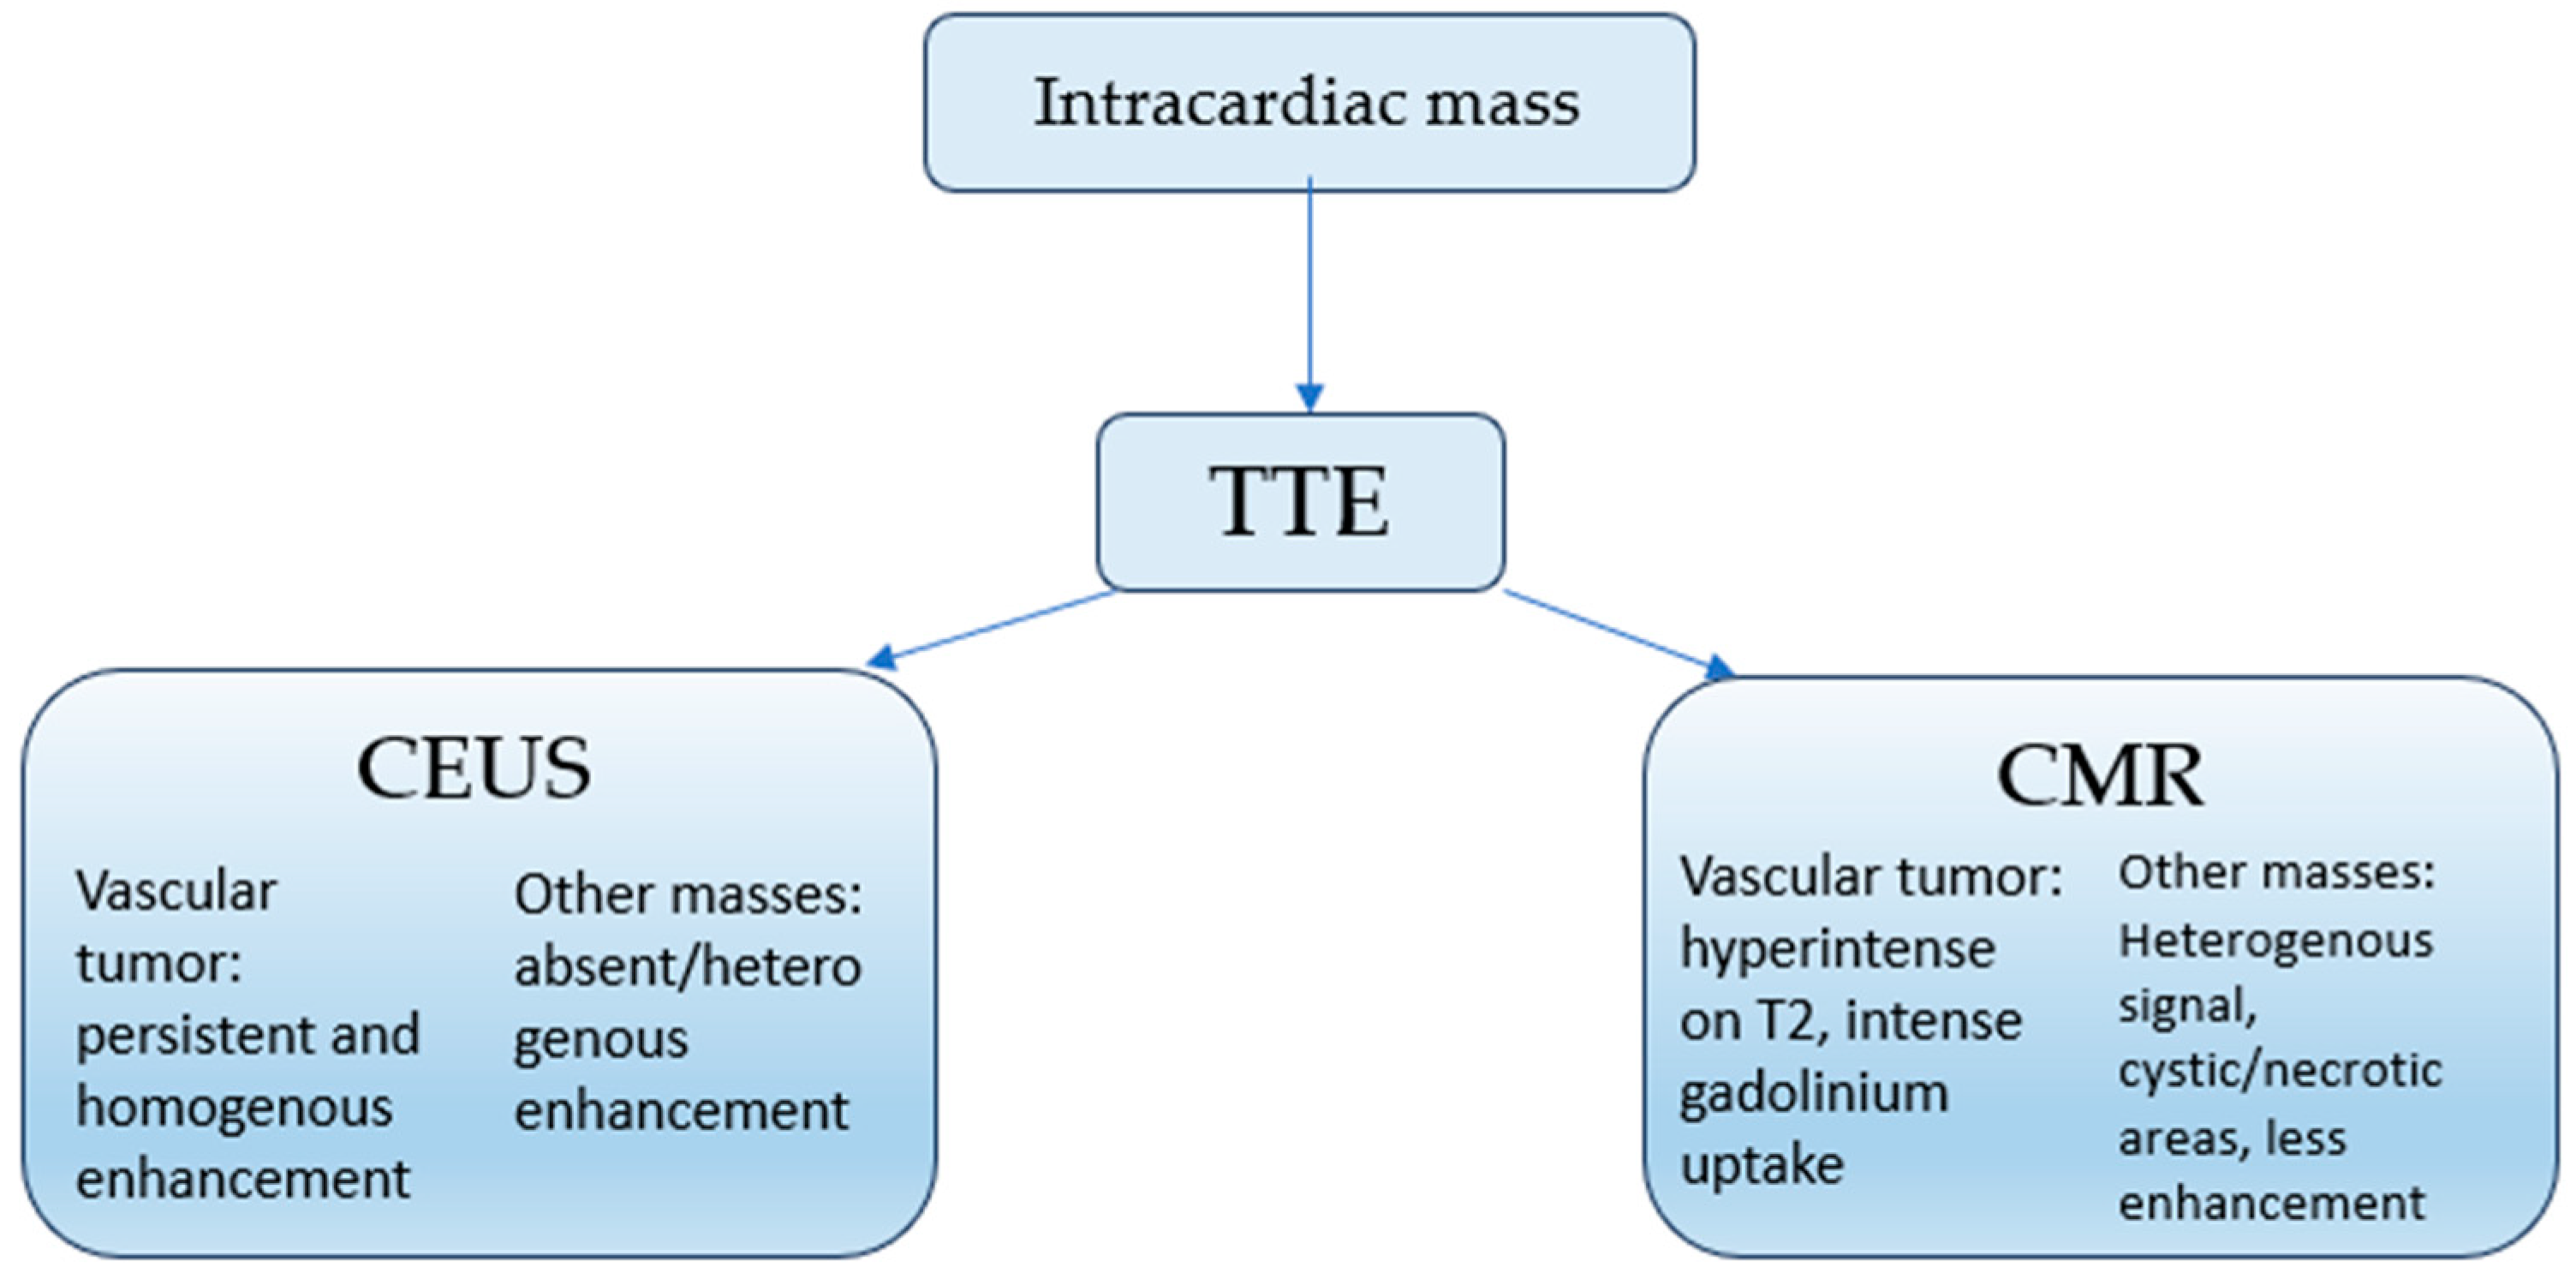

3.2. Proposed Diagnostic Algorithm

- Multimodal imaging—including contrast echocardiography, cardiac MRI, and coronary angiography—should be incorporated into the diagnostic pathway for atrial masses as it may provide valuable preoperative clues and reduce misdiagnosis.